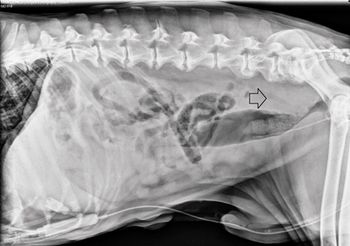

This case hinged on the discovery of a stray air gun pellet in this stray dog, detected by excretory urography.

Veterinary radiologist Dr. Anthony Pease explains why contrast agents are a quick, easy way to examine the urinary tract

Veterinary radiologist Dr. Anthony Pease's thoughts on this quick and easy form of assessment.